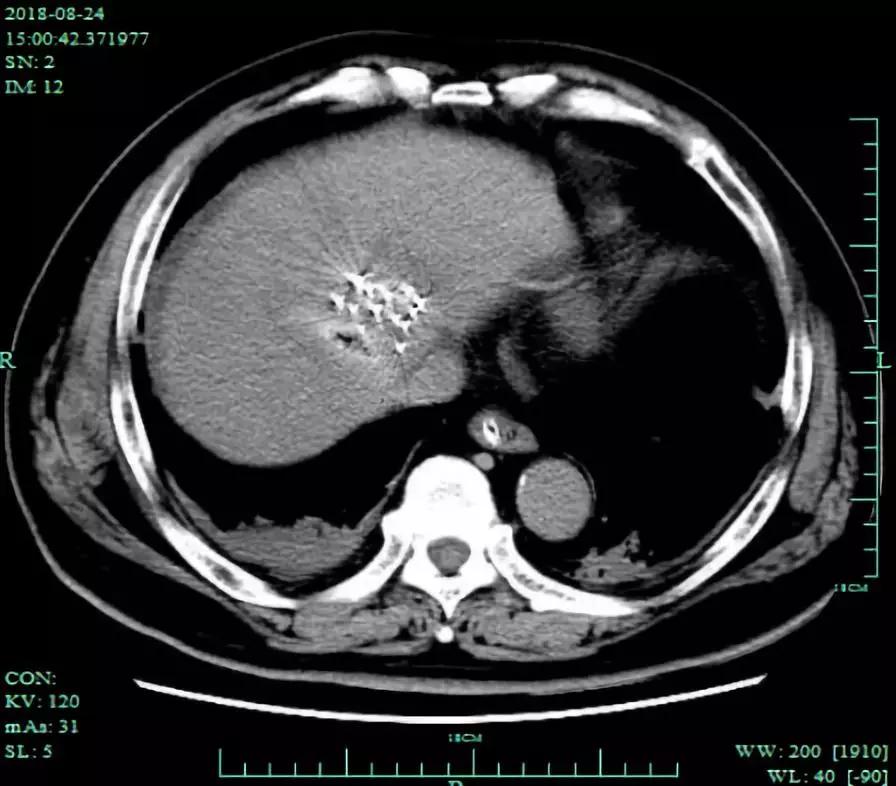

术后CT平扫可见粒子植入位置良好

术后CT和MRI复查,显示粒子植入位置良好,消融病灶完全灭活。

手术名称:肝癌125I粒子植入+微波消融术

手术时间:2018年8月24日